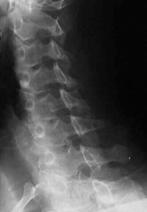

FRACTURA - LUXATIE T12 FRACTURA COMPLEXA DE COLOANA

VERTEBRALA LOMBARA